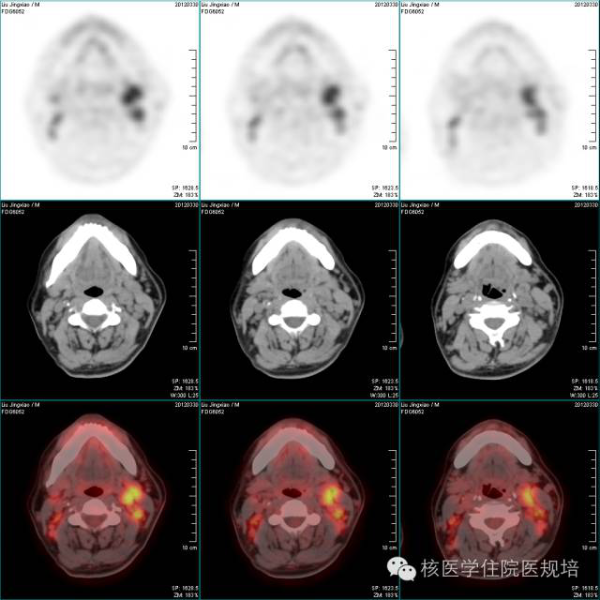

2示双侧颈部多发淋巴结肿大并放射性异常浓聚。

双颈部(图2)、双侧锁骨区、纵隔(图3)、双肺门、双侧胸肌间、双侧腋窝(图3)、右前肋膈角、双膈肌下、腹腔内、腹膜后(图4)、盆腔内及双侧腹股沟区(图5)多发淋巴结肿大并放射性异常浓聚,最大SUV 8.1。脾大,达九个肋单位,实质放射性弥漫增浓,最大SUV 2.9